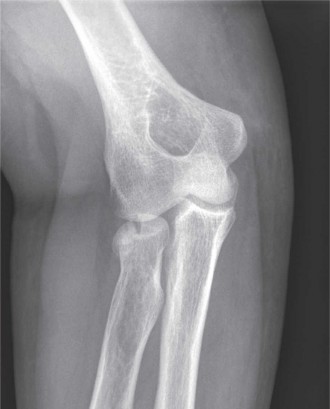

A 36-year-old, right-hand-dominant male presents to the emergency department with right arm and elbow pain af…